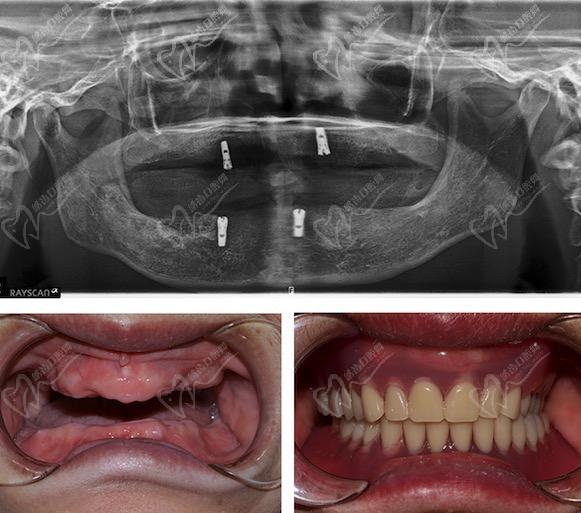

上海松丰齿科蒋勇军医生对瑞典诺贝尔、瑞士ITI、瑞士SIC、韩国奥齿泰、登腾等种植体等经验非常丰富。尤其对于无牙颌种植技术、各类疑难种植技术颇有研究。

来看上海松丰齿科蒋勇军医生种植牙技术咋样?